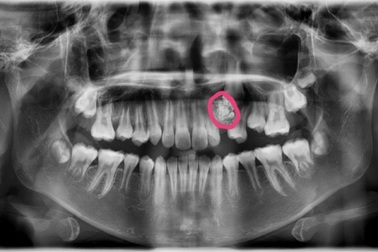

Lý do bất ngờ khiến bé gái 12 tuổi chưa mọc răng nanhBé gái vào viện khám vì răng nanh hàm trên mãi chưa mọc, bác sĩ phát hiện trẻ bị u răng. Gần 20 chiếc răng nhỏ li ti được lấy ra từ khối u răng của trẻ.